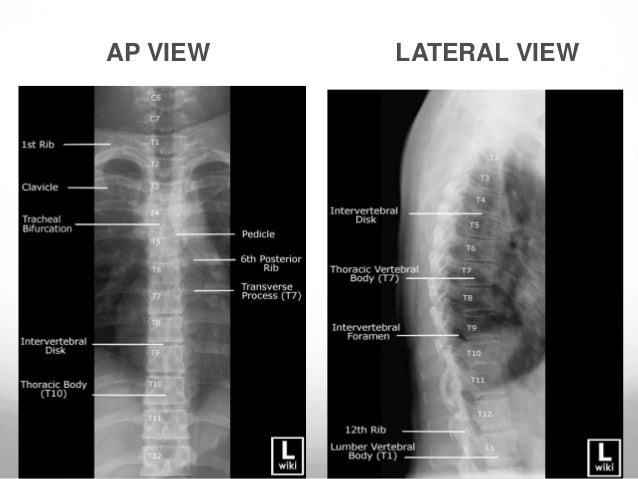

RADIOGRAPHY OF CHEST AND SPINE

radiography t11 distal lumbar intervertebral sacrum spinous vertebral